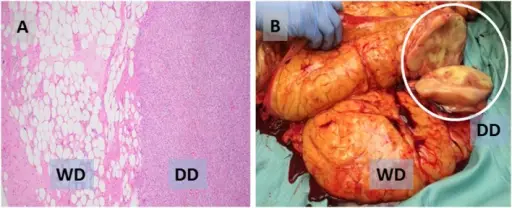

Liposarcoma

Liposarcomas are malignant tumors of adipose tissue.

Definitive diagnosis of liposarcoma is made by pathology showing malignant proliferation of adipose tissue.

Treatment of liposarcomas involves surgical excision.